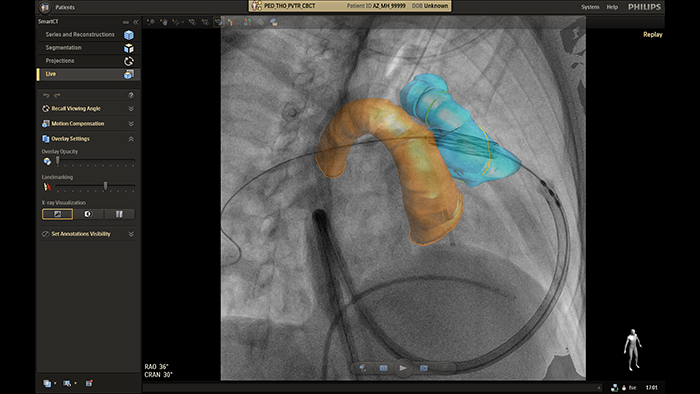

SmartCT live guidance